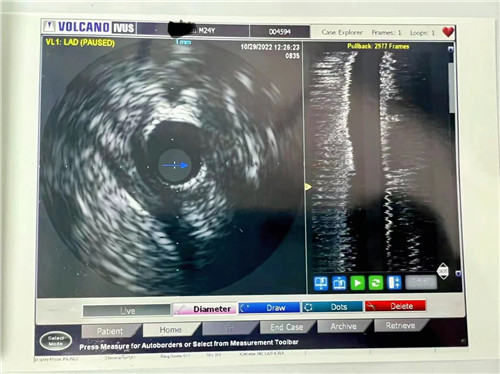

血管內(nèi)超聲提示血管斑塊負(fù)荷66.1%

小貼士:血管內(nèi)超聲(IVUS)

血管內(nèi)超聲(IVUS)是利用導(dǎo)管將一高頻微型超聲探頭導(dǎo)入血管腔內(nèi)進(jìn)行探測,再經(jīng)電子成像系統(tǒng)來顯示心血管組織結(jié)構(gòu)和幾何形態(tài)的微細(xì)解剖信息。它能彌補(bǔ)CAG的不足之處,不僅可準(zhǔn)確測量管腔及粥樣斑塊或纖維斑塊的大小,更重要的是可提供粥樣斑塊的大體組織信息,在顯示因介入治療所致的復(fù)雜病變形態(tài)時明顯優(yōu)于造影。